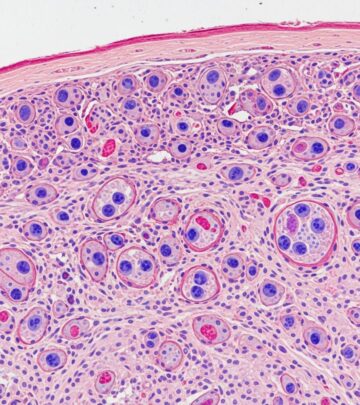

Paracoccidioidomycosis Pathology: Comprehensive Diagnosis Guide